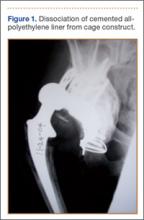

Thirteen patients with major osseous deficiencies of the pelvis were treated using this technique. At mean follow-up of 64.2 months (range, 3-133 months), 10 of the 13 patients had favorable outcomes without further surgery. One patient developed recurrent aseptic loosening that required re-revision, another patient developed recurrent instability that required acetabular liner and femoral head exchange, and a third patient with poor balance fell multiple times. This patient’s ninth fall resulted in dissociation of the acetabular shell from the cage (Figure 3), treated with placement of another cemented multihole metal shell with a standard liner. As dislocations recurred, the liner was changed to a constrained liner (Figure 4). The patient did not have any further dislocations or other hip-related problems. Integrity of cemented shell-cage fixation was maintained in 12 of the 13 patients at final follow-up.